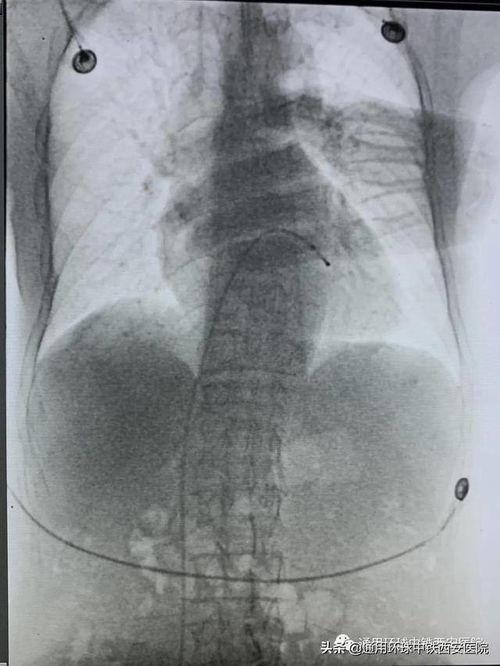

2. 操作步骤:接下来,视频详细介绍了临时起搏器的操作步骤。首先,医生会在患者的胸部进行局部麻醉,然后通过一个小小的切口,将起搏器植入到心脏附近。这个过程中,医生会使用特殊的工具,确保起搏器能够正确地连接到心脏。

3. 连接过程:视频还展示了起搏器与心脏连接的过程。你可以看到,医生将导线从起搏器中引出,并将其连接到心脏的特定位置。这个连接过程需要非常精确,因为只有这样才能保证起搏器能够正常工作。